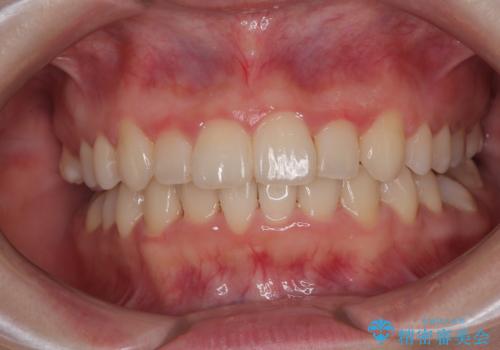

捻れて前に出ている前歯 ワイヤー装置での非抜歯矯正

受け口と八重歯を改善 インビザライン矯正治療